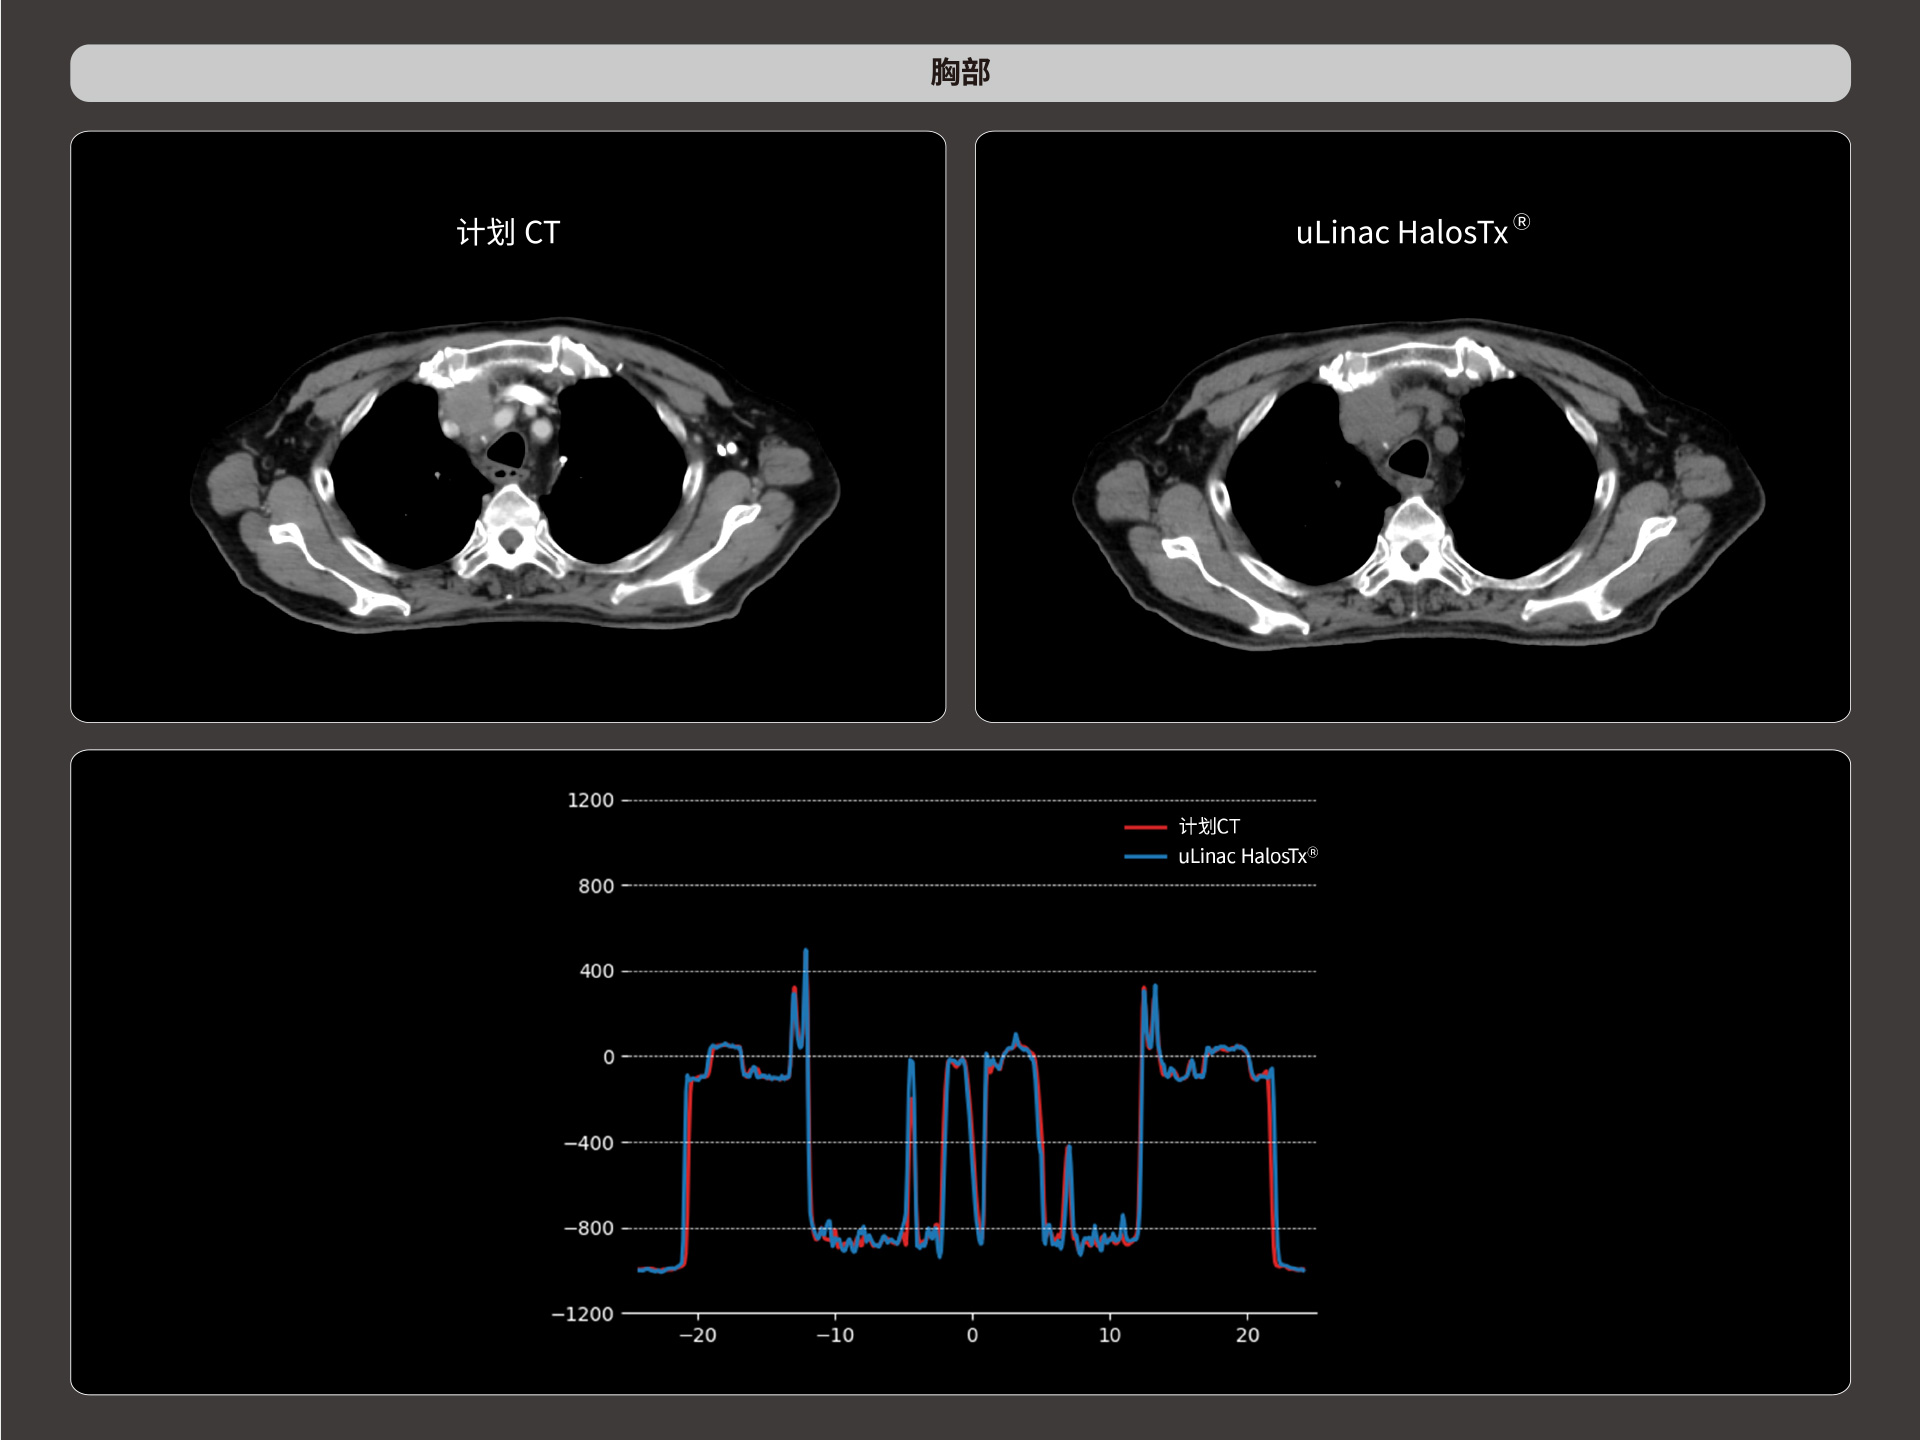

uLinac HalosTx®搭载新一代 87cm 大孔径诊断级CT图像引导系统,全能进阶,实现高清图像质量和全景视野的完美平衡,开辟全疗程 「影像感知」 ,为临床提供更自信、更全面的临床依据。

扇形束成像,极低散射,媲美CT-sim的影像品质

3mm @ 0.3% 高软组织对比度,0.55mm薄层扫描,精确鉴别肿瘤靶区边界

精准CT值,完美满足勾画、剂量计算要求

提供传统 的CT 模拟机所一致的HU值精度(±10HU)

HU金标准